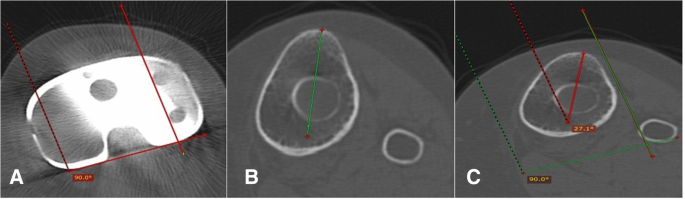

Tibial component rotation

Tibial component rotation was assessed from three axial CT images through the tibia. The geometric center of the tibial plateau was located from an axial image just below the tibial component. The geometric center is axially transposed to an axial image through the prominence of the tibial tuberosity and a line is drawn from the geometric center and the tuberosity, the tibial tuberosity axis. The tibial component axis was drawn at the level of the component polyethylene as a line perpendicular to a line drawn along the posterior surface of the component polyethylene. The tibial tuberosity axis was then axially transposed to this image and the angle between these two lines was measured (Fig. 4).

a Axial computed tomography (CT) image through the tibial component polyethylene showing the tibial component axis, which is defined as the perpendicular to the posterior margin of the component. b Axial CT image through the tibial tuberosity showing the tibial tuberosity axis (T.T.A), which is defined by the line connecting the geometric center of the tibial plateau to the tip of the tibial tubercle. c The T.T.A from b is superimposed on the tibial component axis (T.C.A) from a. The rotation of the tibial component is recorded as the angle subtended by the T.T,A and the T.C.A

The relationship between the tibial tubercle and tibial articular surface was used to assess tibial component rotation, whether internally or externally rotated. The tip of the tibial tubercle is 18° externally rotated from the tibial articular surface. The tibial component was considered neutral in both men and women when internally rotated 18° (±2.6) in relation to the tip of the tibial tuberosity [18]: patients with an angle this range are considered to have tibial component rotational malalignment (outliers) [18].